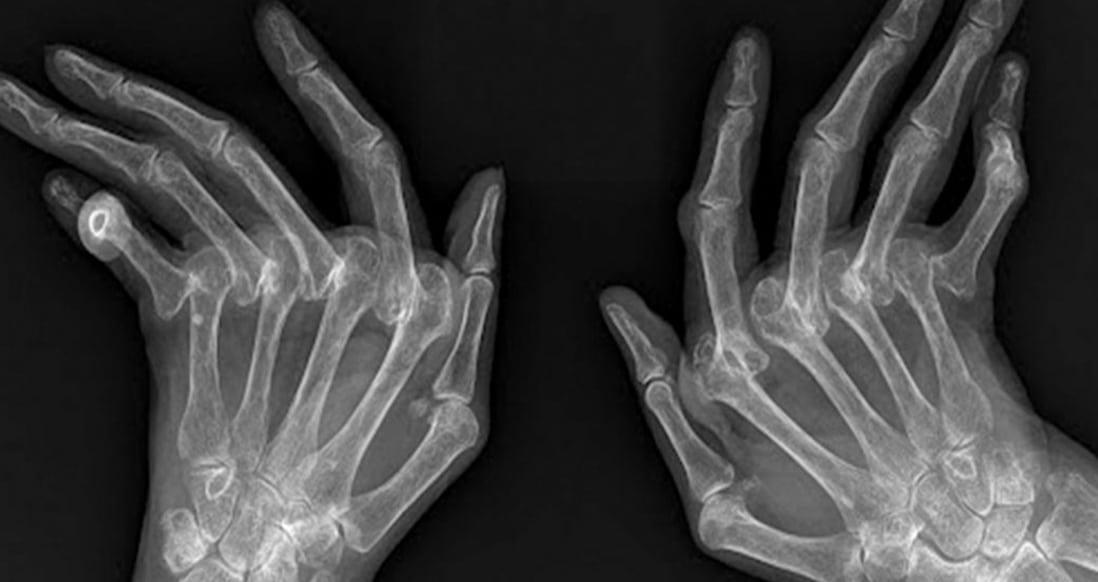

1. Πόνος στις αρθρώσεις: Ο πόνος είναι ένα από τα πρώτα και πιο βασικά συμπτώματα της ΡΑ. Μπορεί να εκδηλωθεί σε οποιαδήποτε άρθρωση του σώματος, όμως συνήθως είναι συμμετρικός στις δύο πλευρές (π.χ. και στους δύο καρπούς ή και στα δύο γόνατα). Σε αρχικό στάδιο, πονούν οι μικρότερες αρθρώσεις, όπως αυτές των δαχτύλων, των καρπών και των αστραγάλων. Ο πόνος μπορεί επίσης να είναι αισθητός στους ώμους, στα ισχία και/ή στα γόνατα.

3. Πρήξιμο: Το πρήξιμο είναι πιο συχνό στους καρπούς ή στις αρθρώσεις των δαχτύλων και πολλές φορές δεν γίνεται εύκολα αντιληπτό από τον γιατρό, όμως δυσκολεύει τον ασθενή να κινηθεί ελεύθερα.